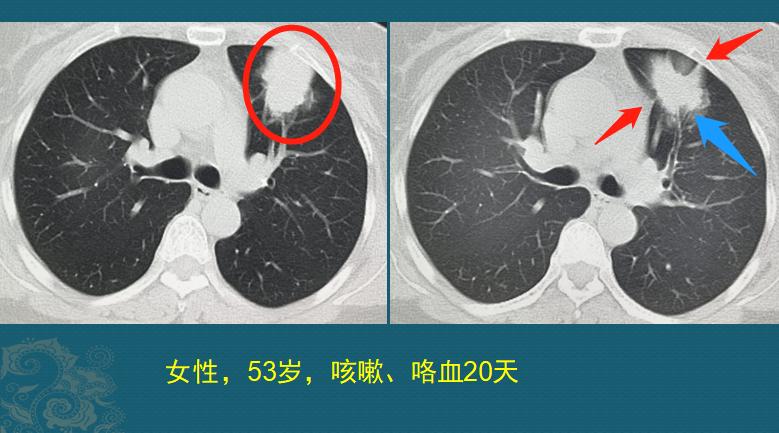

这位女士53岁,咳嗽20天,开始没当回事,吃了些感冒、止咳药没效果,最近这几天开始咯血才觉得不对劲,过来做了胸部CT,肿瘤已经长到4.5cm:

看上图两张CT片,这是一个不规则肿块,长在左肺上叶,最长径4.5cm,蓝箭头显示支气管截断(癌细胞堵塞支气管),红箭头提示肿瘤侵犯壁胸膜和纵隔胸膜,所幸没有肺门和纵隔淋巴结转移,全身检查也未发现远处转移,这个肺癌分期属于II A期(pT2bN0M0)了。